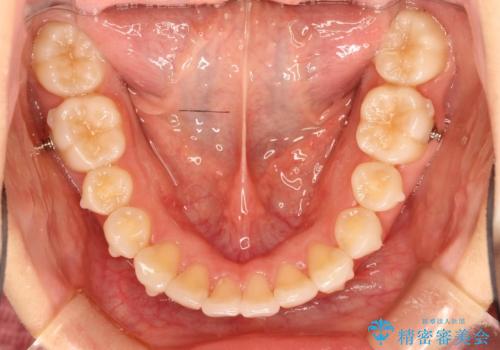

インビザラインで出っ歯を改善する 抜歯をしないinvisalign治療

- 非抜歯・遠心移動による前突の改善をマウスピースにて計画した。

非抜歯矯正の場合、大きく前歯を下げることはできませんが、奥歯の遠心移動や歯のサイズダウンにより歯軸を立て、見かけ上の出っ歯感をある程度改善することができます。